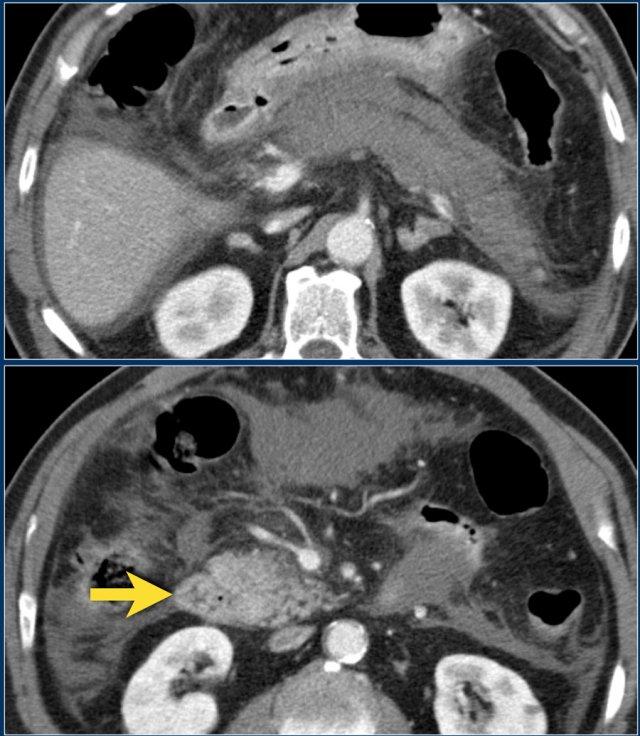

Các hình ảnh cho thấy tụy ngấm thuốc bình thường vào ngày thứ 1.

Khi tình trạng bệnh nhân xấu đi, CT lần hai được thực hiện vào ngày thứ 3.

Lưu ý phần lớn thân và đuôi tụy không còn ngấm thuốc, gợi ý viêm tụy hoại tử (các mũi tên).

CT lần đầu đã đánh giá thấp mức độ nặng của viêm tụy.

Bệnh nhân này tử vong vào ngày thứ 5 do hội chứng đáp ứng viêm hệ thống (SIRS) nặng và suy đa tạng.